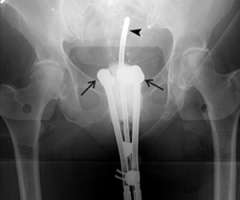

In the images below for example on the right is an anterior-posterior view of a vaginal applicator inserted in the vagina. You can see the cylinder pushing up against the top of the vaginal apex. You can't see the outline of the entire bladder and rectum but one way to approximate them is to place foley catheters in the bladder (yellow outline) and the rectum (brown outline) so they can be visualized.

Our approach at UCLA is to do 3D based instead of 2D based planning for these cases as well. Once again one can immediately appreciate how much additional detail in the anatomy and distribution of the radiation dose can be appreciated on the CT scan versus the X-ray.

ovoid applicator

Example of 2D based planning using a tandem and ovoid applicator